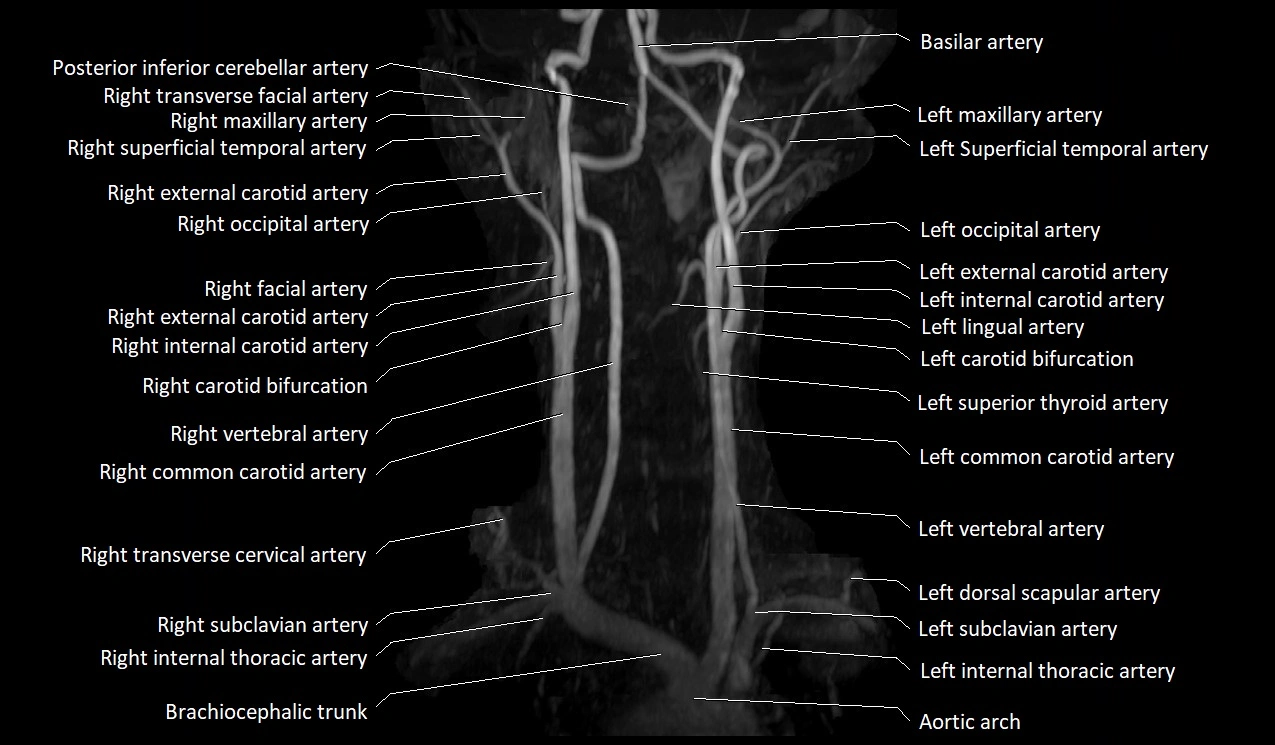

CTA (CT Angiography):

• Enhances brightly with intravenous contrast

• Easily visualized on arterial and especially venous phase images

• Shows continuity with external jugular vein or subclavian vein